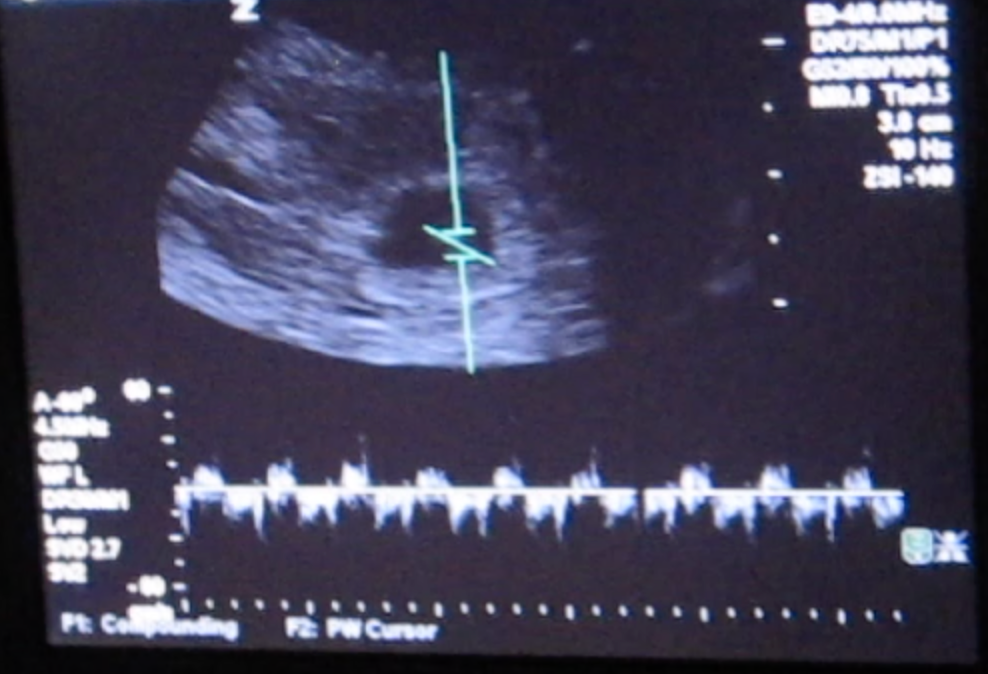

Our first appointment was exciting. Without a hitch. We even got to hear the baby’s heartbeat! We thought nothing of it when the OB-GYN asked me to remind her when the first day of my last period was, and if there was any chance it had been late. Nothing to worry about, she said – sometimes they track a little small but most of the time they catch up, and due dates can always be a little off.

The technician spent a long time with us. She kept moving the probe around for what seemed like a full half hour, as if she was looking as hard as I was praying. When we asked, she said she isn’t allowed to interpret what she sees, that she can only share the report with the physician who then interprets for us. We were wheeled back to our little room in the emergency department and waited and waited. When the on-call OB came in, she confirmed the worst, with a tone of voice indicating that despite having had to deliver the message time and time again, it never got easier: “We couldn’t find a heartbeat. I’m sorry.”